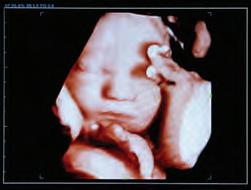

The Premier 3D/4D HD Elective Ultrasound Studio in Fargo CAPTURE THE FIRST MOMENTS OF YOUR BABY’S LIFE IN COLOR Services: � Early Gender Determination Starting at 8 weeks � 3D/4D HD Ultrasound Packages Call (701) 630-1100 or schedule online at BloomingBabyUltrasoundHD.com 3202 13TH AVENUE SOUTH, FARGO, ND | 701.232.8903 | SCHEELSHOMEANDHARDWARE.COM | Connect with us @scheelshardware Fall inLove WITH NEW STYLES NEW FOR FALL 2020